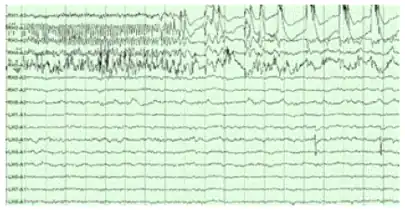

The hippocampus shows two major modes of activity, each associated with a distinct pattern of neural population activity and waves of electrical activity as measured by an electroencephalogram (EEG). These modes are named after the EEG patterns associated with them: theta and large irregular activity (LIA). The main characteristics described below are for the rat, which is the animal most extensively studied.[112]

The theta mode appears during states of active, alert behavior (especially locomotion), and also during REM sleep (dreaming).[113] In the theta mode, the EEG is dominated by large regular waves with a frequency range of 6 to 9 Hz, and the main groups of hippocampal neurons (pyramidal cells and granule cells) show sparse population activity, which means that in any short time interval, the great majority of cells are silent, while the small remaining fraction fire at relatively high rates, up to 50 spikes in one second for the most active of them.[114][115] An active cell typically stays active for half a second to a few seconds. As the rat behaves, the active cells fall silent and new cells become active, but the overall percentage of active cells remains more or less constant. In many situations, cell activity is determined largely by the spatial location of the animal,[116] but other behavioral variables also clearly influence it.

The LIA mode appears during slow-wave sleep (non-dreaming), and also during states of waking immobility such as resting or eating.[113] In the LIA mode, the EEG is dominated by sharp waves that are randomly timed large deflections of the EEG signal lasting for 25–50 milliseconds. Sharp waves are frequently generated in sets, with sets containing up to 5 or more individual sharp waves and lasting up to 500 ms. The spiking activity of neurons within the hippocampus is highly correlated with sharp wave activity. Most neurons decrease their firing rate between sharp waves; however, during a sharp wave, there is a dramatic increase in firing rate in up to 10% of the hippocampal population.[117]

Hippocampal theta rhythm

The underlying currents producing the theta wave are generated mainly by densely packed neural layers of the entorhinal cortex, CA3, and the dendrites of pyramidal cells. The theta wave is one of the largest signals seen on EEG, and is known as the hippocampal theta rhythm.[119] In some situations the EEG is dominated by regular waves at 3 to 10 Hz, often continuing for many seconds. These reflect subthreshold membrane potentials and strongly modulate the spiking of hippocampal neurons and synchronize across the hippocampus in a travelling wave pattern.[120] The trisynaptic circuit is a relay of neurotransmission in the hippocampus that interacts with many brain regions. From rodent studies it has been proposed that the trisynaptic circuit generates the hippocampal theta rhythm.[121]

Theta rhythmicity previously clearly shown in rabbits and rodents has also been shown in humans.[122] In rats (the animals that have been the most extensively studied), theta is seen mainly in two conditions: first, when an animal is walking or in some other way actively interacting with its surroundings; second, during REM sleep.[123] The function of theta has not yet been convincingly explained although numerous theories have been proposed.[112] The most popular hypothesis has been to relate it to learning and memory. An example would be the phase with which theta rhythms, at the time of stimulation of a neuron, shape the effect of that stimulation upon its synapses. What is meant here is that theta rhythms may affect those aspects of learning and memory that are dependent upon synaptic plasticity.[124] It is well established that lesions of the medial septum – the central node of the theta system – cause severe disruptions of memory.[125] However, the medial septum is more than just the controller of theta; it is also the main source of cholinergic projections to the hippocampus.[19] It has not been established that septal lesions exert their effects specifically by eliminating the theta rhythm.[126]

Sharp waves

During sleep or during resting, when an animal is not engaged with its surroundings, the hippocampal EEG shows a pattern of irregular slow waves, somewhat larger in amplitude than theta waves. This pattern is occasionally interrupted by large surges called sharp waves.[127] These events are associated with bursts of spike activity lasting 50 to 100 milliseconds in pyramidal cells of CA3 and CA1. They are also associated with short-lived high-frequency EEG oscillations called "ripples", with frequencies in the range 150 to 200 Hz in rats, and together they are known as sharp waves and ripples. Sharp waves are most frequent during sleep when they occur at an average rate of around 1 per second (in rats) but in a very irregular temporal pattern. Sharp waves are less frequent during inactive waking states and are usually smaller. Sharp waves have also been observed in humans and monkeys. In macaques, sharp waves are robust but do not occur as frequently as in rats.[118]